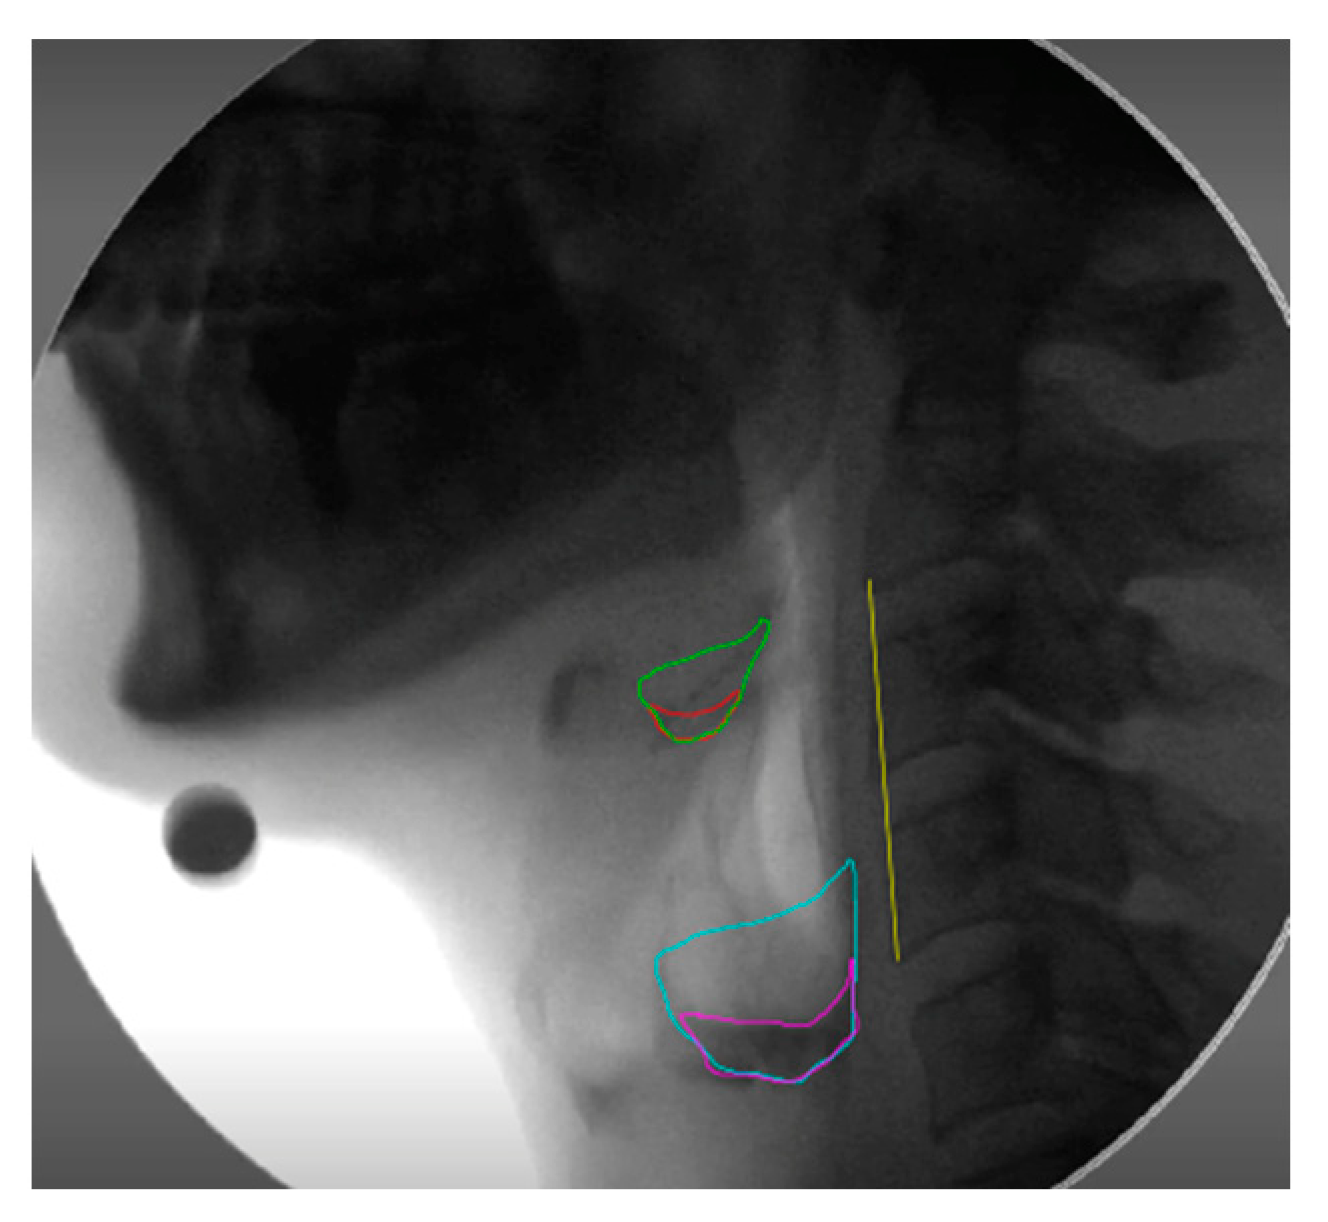

The videofluoroscopy recordings were analyzed frame-by-frame to determine when the hyoid had returned to the resting position after the first swallow. A take on the normalized residue ratio scale (NRRS) [9] was incorporated in MATLAB to measure post-swallow residue in the vallecular space (v) and pyriform sinuses (p). The imfreehand and imline tools were used to outline the structural spaces, residue area, and C2-C4 scale length. The vallecular space was defined anteriorly by the perpendicular spine adjacent to the tip of the epiglottis and posteriorly by the epiglottis. The pyriform sinuses were defined using a line extending from the tip of the arytenoid shadow to the posterior pharyngeal wall, perpendicular to the vertebral axis. Each segmentation measured was overlaid on the final image (Figure 4), where the segmented areas and spinal distance were used to determine the NRRS values.

Figure 4.

Lateral VFSS frame post-swallow. Outlined is the vallecular space (green), vallecular residue (red), pyriform sinus (blue), pyriform sinus residue (pink), and anatomical scalar C2-C4 (yellow).